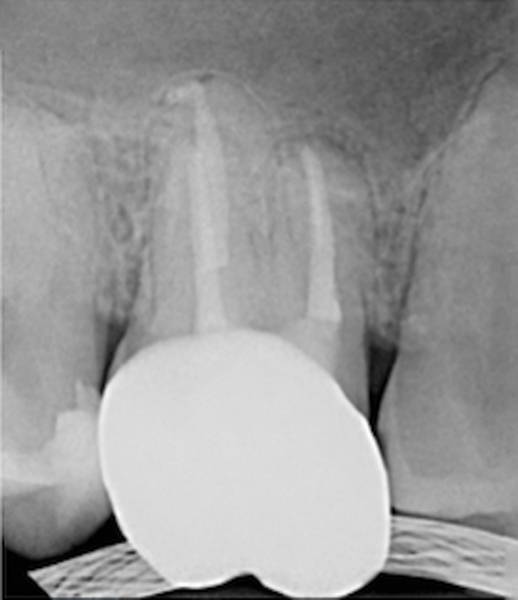

Fig 11. Preoperative radiograph. Courtesy of Dr. Guillaume Jouanny.

Figure 11

Fig 12. Postoperative radiography after full pulpotomy was performed. Courtesy of Dr. Guillaume Jouanny.

Figure 12

Fig 13. Tooth was asymptomatic at 1-year follow-up. Courtesy of Dr. Guillaume Jouanny.

Figure 13

Fig 14. Contralateral tooth at 1-year follow-up. Courtesy of Dr. Guillaume Jouanny.

Figure 14

In this case, the tooth tested vital but showed clinical signs of irreversible pulpitis. Treatment with a full pulpotomy was chosen to improve the chances the remaining pulp would survive and remain healthy. The preoperative radiograph in Figure 11 shows extensive caries in the tooth and a slightly widened apical periodontal ligament. A full pulpotomy was performed using the BC putty (Figure 12). After the putty set, a coronal restoration was placed, and an immediate postoperative radiograph was taken and viewed. At the 1-year follow-up, the tooth was asymptomatic, and the radiograph showed continued root development (Figure 13), a healthy apical periodontium, and, importantly, no calcifications in the remaining pulp (as is often seen with a calcium hydroxide therapy). A radiograph taken of the contra-lateral tooth showed similar root development (Figure 14).